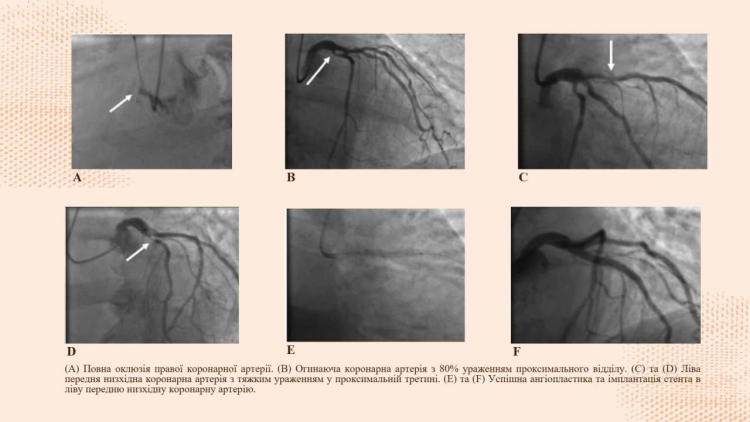

The students presented the report titled «Aslanger’s Pattern as a Predictor of Multivessel Coronary Artery Disease and Acute Occlusion in Patients with Acute Coronary Syndrome» and took 2nd place in the «Internal Medicine II» section.